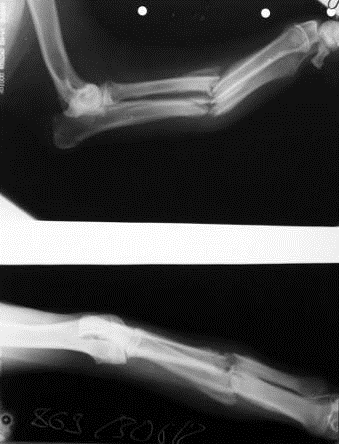

Рентгеновское исследование.

Проведённая рентген-диагностика выявила диафизарный перелом локтевой и лучевой костей левой грудной конечности.

На момент поступления больного животного в клинику на основании анамнеза и клинических признаков при первичном осмотре был поставлен предварительный диагноз: перелом костей предплечья левой грудной конечности.

Позже, уже при детальном, более углубленном обследовании животного на основании сложившейся клинической картины предварительный диагноз был подтвержден.

При пальпации отмечалось следующее: ярко выраженная болезненность в области патологического очага, деформация кости в диафизе предплечья, костная крепитация, легкое укорочение конечности. Также при визуальном осмотре припухлость в месте предполагаемого перелома с незначительным повышением температуры относительно общей температуры тела, измерение которой (ректально) показало нормативный показатель - 38,7°С. Рентген-диагностика подтвердила предполагаемый диагноз.